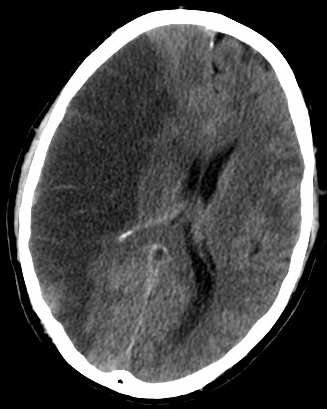

K.J.F.: To prawda, te liczby robią wrażenie, ale trzeba pamiętać, że do tych chorób zaliczamy nie tylko zawały serca, ale także udary mózgu. Co więcej – dzisiaj większym problemem niż zawały, stają się właśnie udary. Z zawałami dobrze sobie radzimy, potrafimy je dobrze leczyć, więc wydłużamy życie naszym pacjentom. Natomiast udary występują u ludzi dekadę, dwie dekady później niż zawał serca. Dlatego, choć udało się zredukować śmiertelność z powodu zawału serca, takich sukcesów nie mamy z udarami mózgu, które skutkują zgonem lub trwałym inwalidztwem i koniecznością opieki osób trzecich.

PAP: Skąd się biorą te udary?

K.J.F.: Udary mózgu i zawały serca mają dokładnie taką samą etiologię, czynniki ryzyka ich wystąpienia są identyczne.

To nadciśnienie tętnicze, zaburzenia lipidowe, cukrzyca, palenie papierosów oraz nadwaga / otyłość. W przypadku udaru niedokrwiennego mózgu dochodzi kilka innych czynników ryzyka – w tym niezdiagnozowane / nieleczone migotanie przedsionków.

Gdyby wyeliminować u każdej osoby te czynniki ryzyka – co zostało potwierdzone w różnych badaniach epidemiologicznych na świecie – ryzyko zawału bądź udaru zmniejszyłoby się o 90 proc.